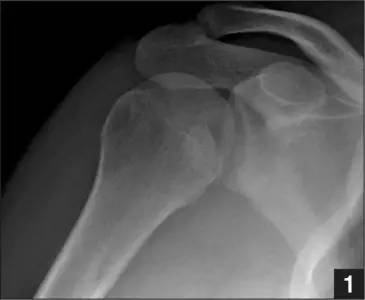

正位片示肱骨头损伤(来源:Anatomical Reconstruction of Reverse Hill-Sachs Lesions Using the Underpinning Technique. Orthopedics May 2012 - Volume 35 · Issue 5: e752-e757)

肩关节前脱位时发生的肱骨头后外侧凹陷性骨折,是经典的 Hill-Sachs 损伤(Hill-Sachs lesion);

而肩关节后脱位时发生的肱骨头前内侧凹陷性骨折,是反 Hill-Sachs 损伤(Reverse Hill-Sachs lesion/ McLaughlin lesion)。